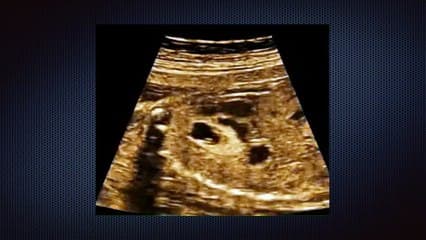

La médiathèque du Collège Français d'Échographie Fœtale (CFEF) constitue l'une des plus importantes collections de ressources vidéo dédiées à l'échographie fœtale en France. Avec plus de 3 261 vidéos, elle couvre l'ensemble des thématiques liées à la pratique échographique prénatale.

Vous y trouverez des conférences présentées lors des congrès nationaux et internationaux, des cours magistraux dispensés par des experts reconnus, des démonstrations pratiques sur des cas cliniques réels, ainsi que des podcasts et tables rondes sur les dernières avancées de la spécialité.